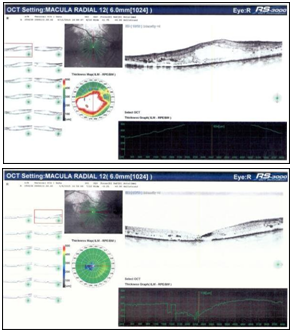

Figure 2 shows the optical coherence tomography (OCT) radial scan of the macula before and after IVTA treatment. Figure 3 shows the trend of macular thickness (a), flicker ERG implicit time (b) and IOP (c). Slit lamp examination of the RE anterior segment revealed moderate lens opacity while in the LE it showed iris and angle NVs, fixed mydriasis, pseudoexfoliation of lens capsule and mild lens opacity. The fundus examination of both eyes showed diabetic retinopathy with hemorrhages, microaneurysms, hard exudates and clinically significant macular edema in the RE with subfoveal and perifoveal hard exudates. Macular thickness measured with the OCT was 634 μm in the RE and 200μm in the LE. Flicker ERG implicit time was 36.64 ms in the RE and 42.15 ms in the LE.

Figure 2 Morphological analysis of the right eye. A) OCT macular thickness soon before IVTA; B) OCT macular thickness 6 months after IVTA.

An IVTA was proposed for both eyes commencing with the LE. Therefore, a first injection of 4 mg (0.05 ml) triamcinolone acetonide (Taioftal ®, Sooft Italia S.p.A, IT) was performed in the LE. After one month, visual acuity was still CF, but iris and angle NVs were barely visible both at slit lamp examination and gonioscopy. IOP was reduced to 17mmHg and the fundus examination showed a marked reduction of the hard exudates. After two months follow-up, BCVA in the LE increased to 20/100 and no iris and angle NVs were detectable at slit lamp examination. IOP further decreased to 12 mmHg. Hard exudates were strongly decreased at fundoscopy, OCT macular thickness was 196μm and flicker ERG implicit time decreased to 38.50 ms. After six months follow-up, BCVA remained stable at 20/100 while IOP returned to 42 mmHg. Iris and angle NVs reappeared and were detectable both at slit lamp examination and gonioscopy. Fundus examination showed no reappearance of hard exudates, OCT macular thickness was stable at 221μm, whilst flicker ERG implicit time returned to 40.53 ms. 25 days after the IVTA in the LE, an injection of 4 mg (0,05 ml) triamcinolone acetonide (Taioftal ®) was given also in the RE. At one month follow- up NCVA was still 20/400, IOP was 13 mmHg and OCT macular thickness already decreased to 229μm. At fundus examination subfoveal and perifoveal hard exudates were reduced together with the entity of DME. Flicker ERG implicit time was 37.61 ms. Five months after treatment, visual acuity was improved to 20/100, IOP was 20 mmHg and fundus examination revealed a further reduction of the hard exudates and of the DME (macular thickness 116μm). Flicker ERG implicit time decreased to 33.07 ms.

This case illustrates the usefulness, safety and efficacy of intravitreal injections of triamcinolone acetonide in a patient with diabetic macular edema in the right eye and pseudoexfoliative glaucoma complicated by iris and angle neovessels in the left eye. During the 6 months observation period all the parameters under analysis were improving. Most notably, OCT showed a rapid important thinning of the macular area in the RE. Flicker ERG implicit time, as demonstrated in previous studies,10,11 is a quantifiable objective measurement of photoreceptor damage in different types of retinal diseases. In this case, its initial values were above the normality threshold of 34 ms10 in both eyes. After IVTA in the RE we observed a decrease of its value below the normality threshold (33.07 ms at 6 months) that was concomitant with the normalization of macular thickness at 116µm and a modest increase of visual acuity. In contrast, flicker ERG values in the glaucomatous LE remained stable, above the normality threshold, despite some improvement of the visual acuity.